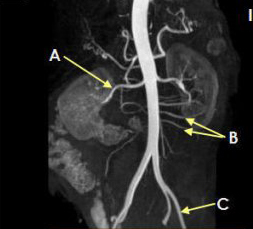

Letter A in Image 179 is pointing to

Right renal artery

Letter B in Image 179 is pointing to:

Branches of mesenteric artery

: Letter C in Image 179 is pointing to

External iliac artery